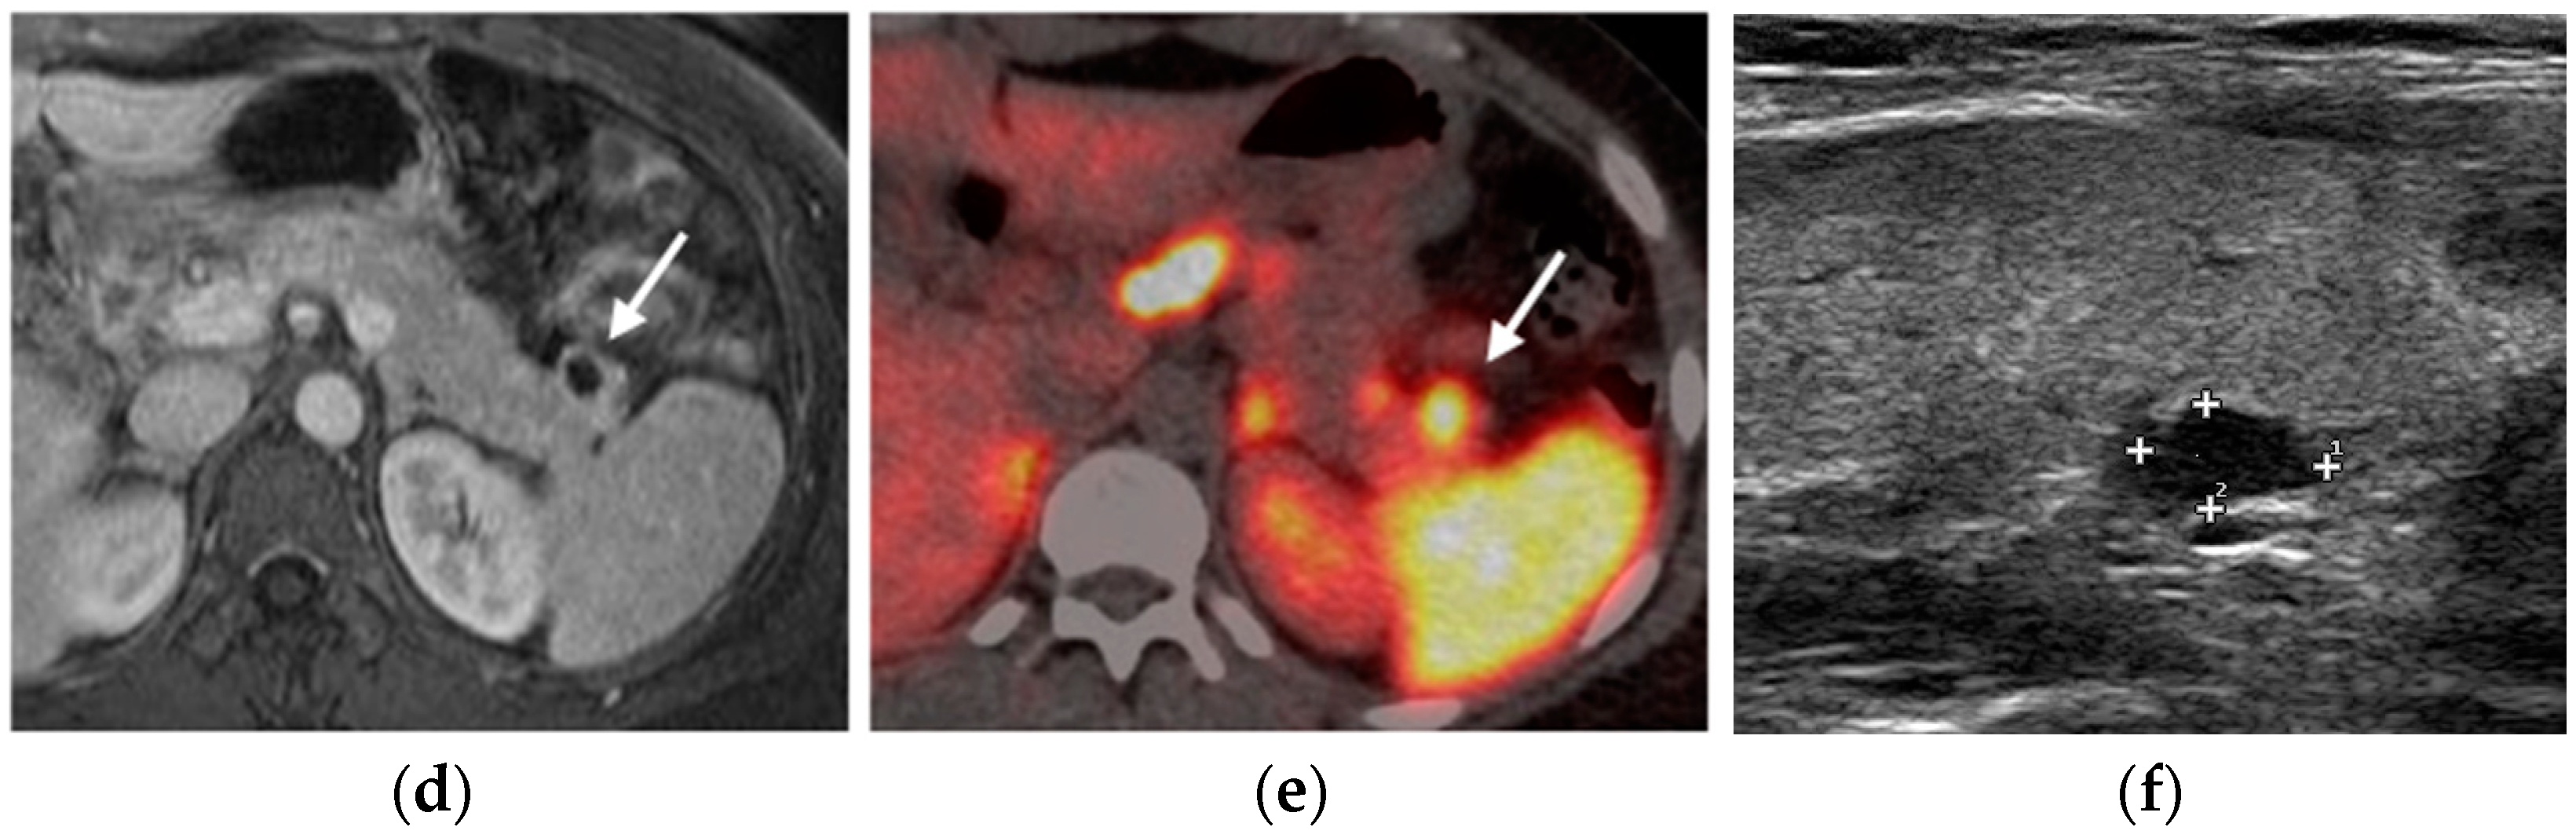

PNETs exhibit varying signal intensity with Diffusion-Weighted Imaging (DWI), but they often demonstrate restricted diffusion, with smaller lesions potentially being not easily detected on other MRI sequences [17]. Less differentiated tumors demonstrate even more diffusion restriction (Figure 6).

Figure 6.

Insulinoma. Heterogeneously enhancing mass (arrows) in the pancreatic tail (a), with significant diffusion restriction (b,c) and avid uptake on PET-CT (d).

After contrast administration, pNETs show hyperintensity in the arterial phase.